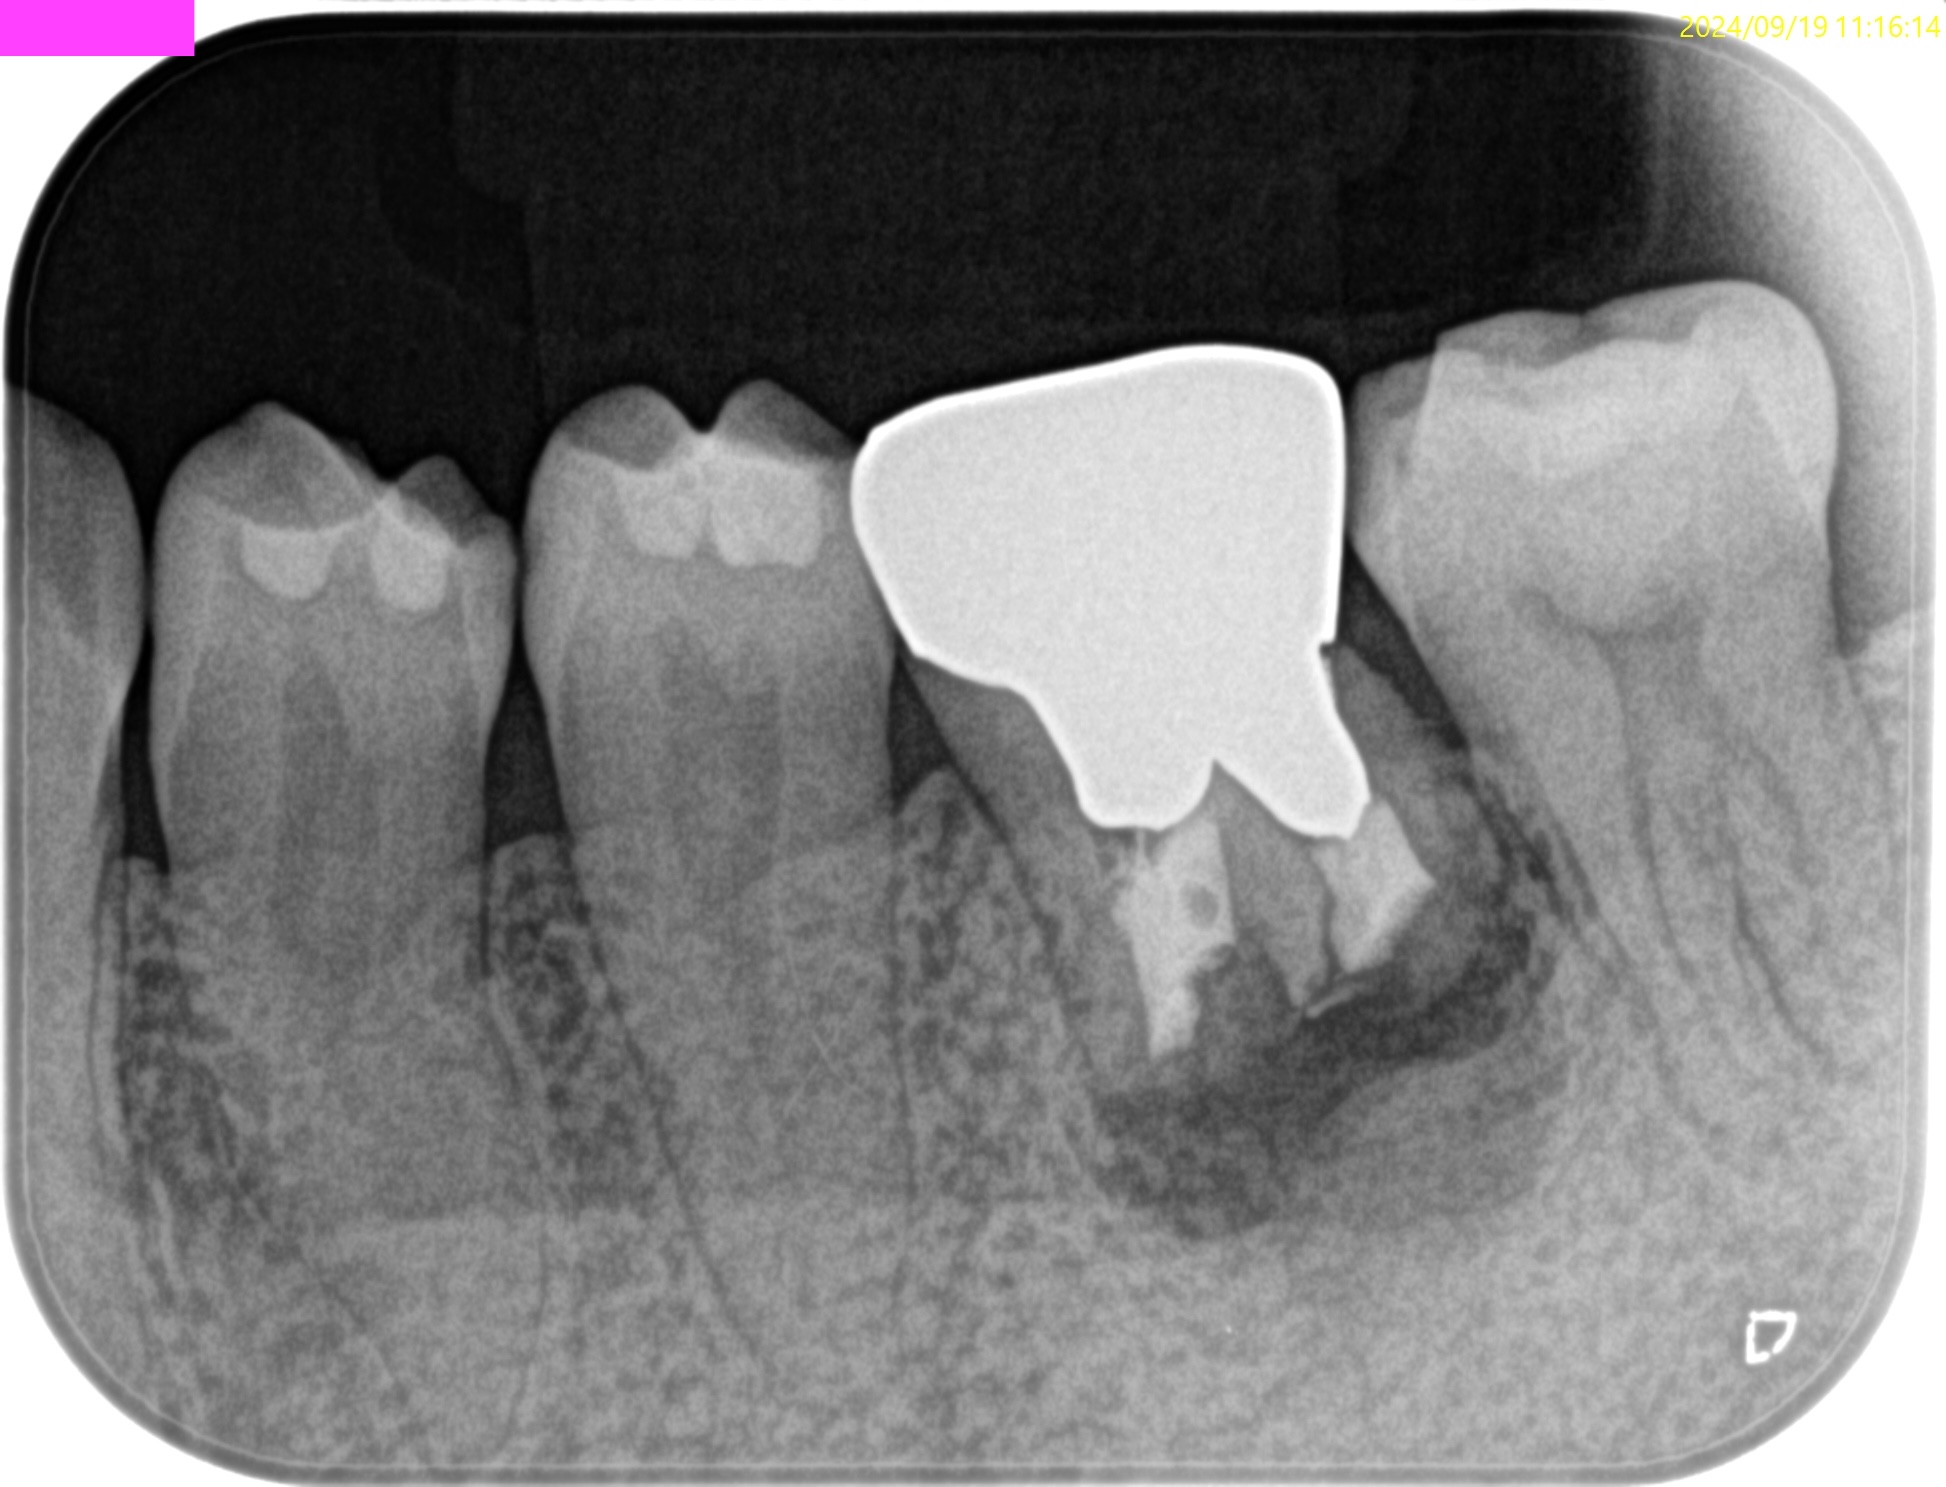

術後にPA, CBCTを撮影した。

M

D

問題はないだろう。

最後に縫合して終了した。

この1ヶ月後に、支台築造のみを行ったが、

Sinus tractはすでに消失していた。

以下のようにPA,CBCTはなった。